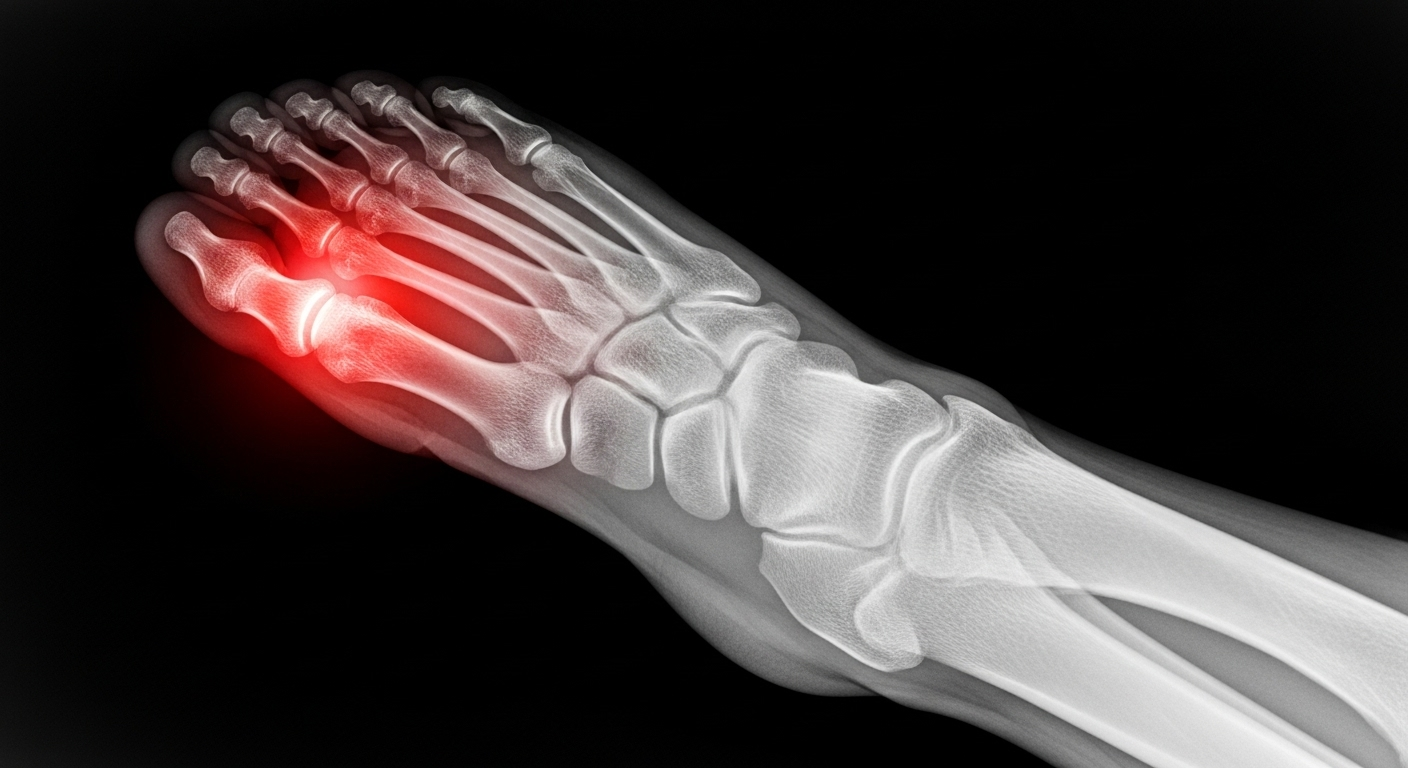

La goutte, c’est une forme d’arthrite très douloureuse. Elle se déclenche quand il y a trop d’acide urique dans le sang. Cet excès d’acide urique finit par former de minuscules cristaux pointus, comme des petites aiguilles, qui se déposent dans les articulations (souvent le gros orteil). La douleur intense vient du fait que notre système immunitaire, en voyant ces cristaux, les considère comme des ennemis et les attaque, ce qui crée une inflammation très forte.